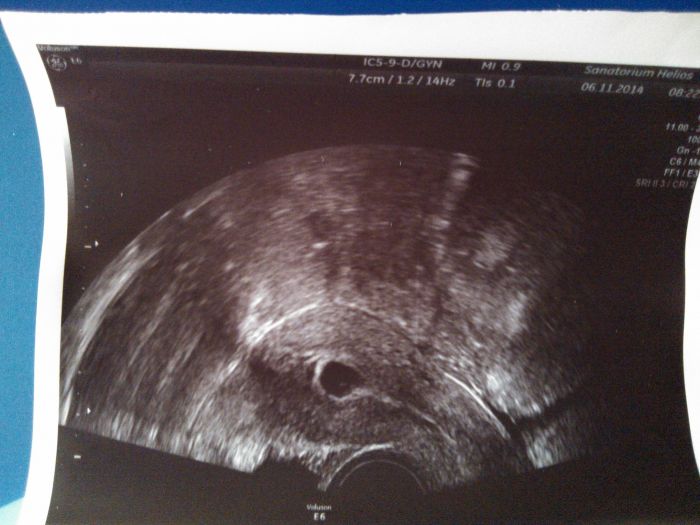

ale poté naštěstí UTZ a mimi tam je - je tam 1. Měla jsem prý hematon - vypadl ze mě cca 3 cm veliký kus ,,játry,, prostě cucek jak prase

vůbec nemám ještě vyhrano....Bolesti už ustoupily,a už se mi zdá že ustává i krvácení, ale mazec, bylo to jako silná MS :-( Ale z krve i z UTZ, je vše ok. Mám šílený strach

co si o tom myslíte holky? V pondělí jdu znova a rozhodne se - musí být srdíčko..... a musím přestat krvácet, jako z toho cucku mám dost....to jsem ještě nikdy nezažila.....Musím se modlit aby vše bylo do pondělí OK..... v pondělí jdu zase na UTZ.